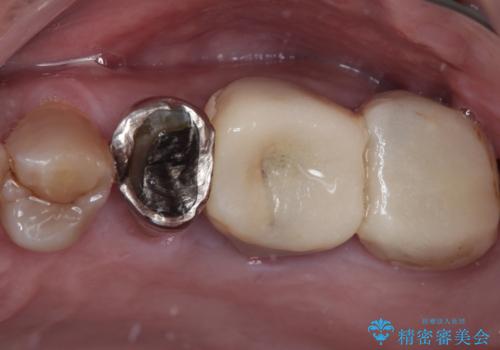

下顎大臼歯の再根管治療とオールセラミッククラウンによる補綴治療

奥歯がうずく